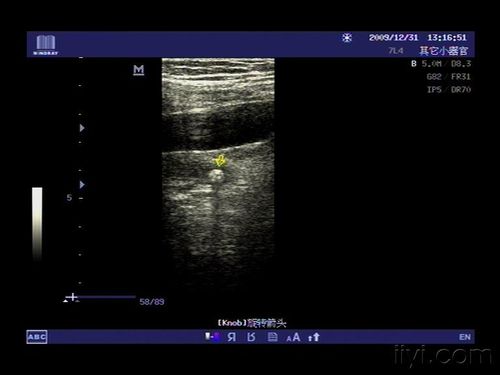

再看一例左侧输尿管中段的结石,位于髂血管分叉稍下方